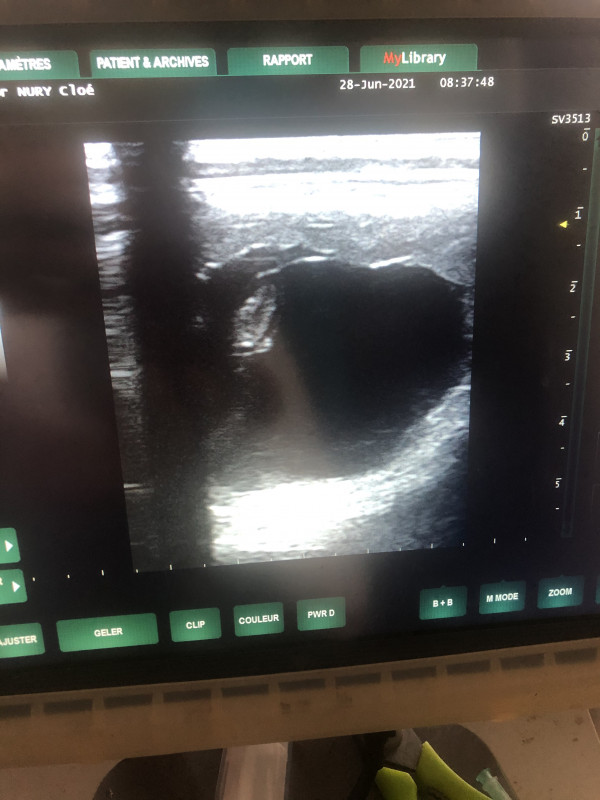

Ici tous va bien, DG des 30 jours toujours ok et on a vu son petit c?ur ?